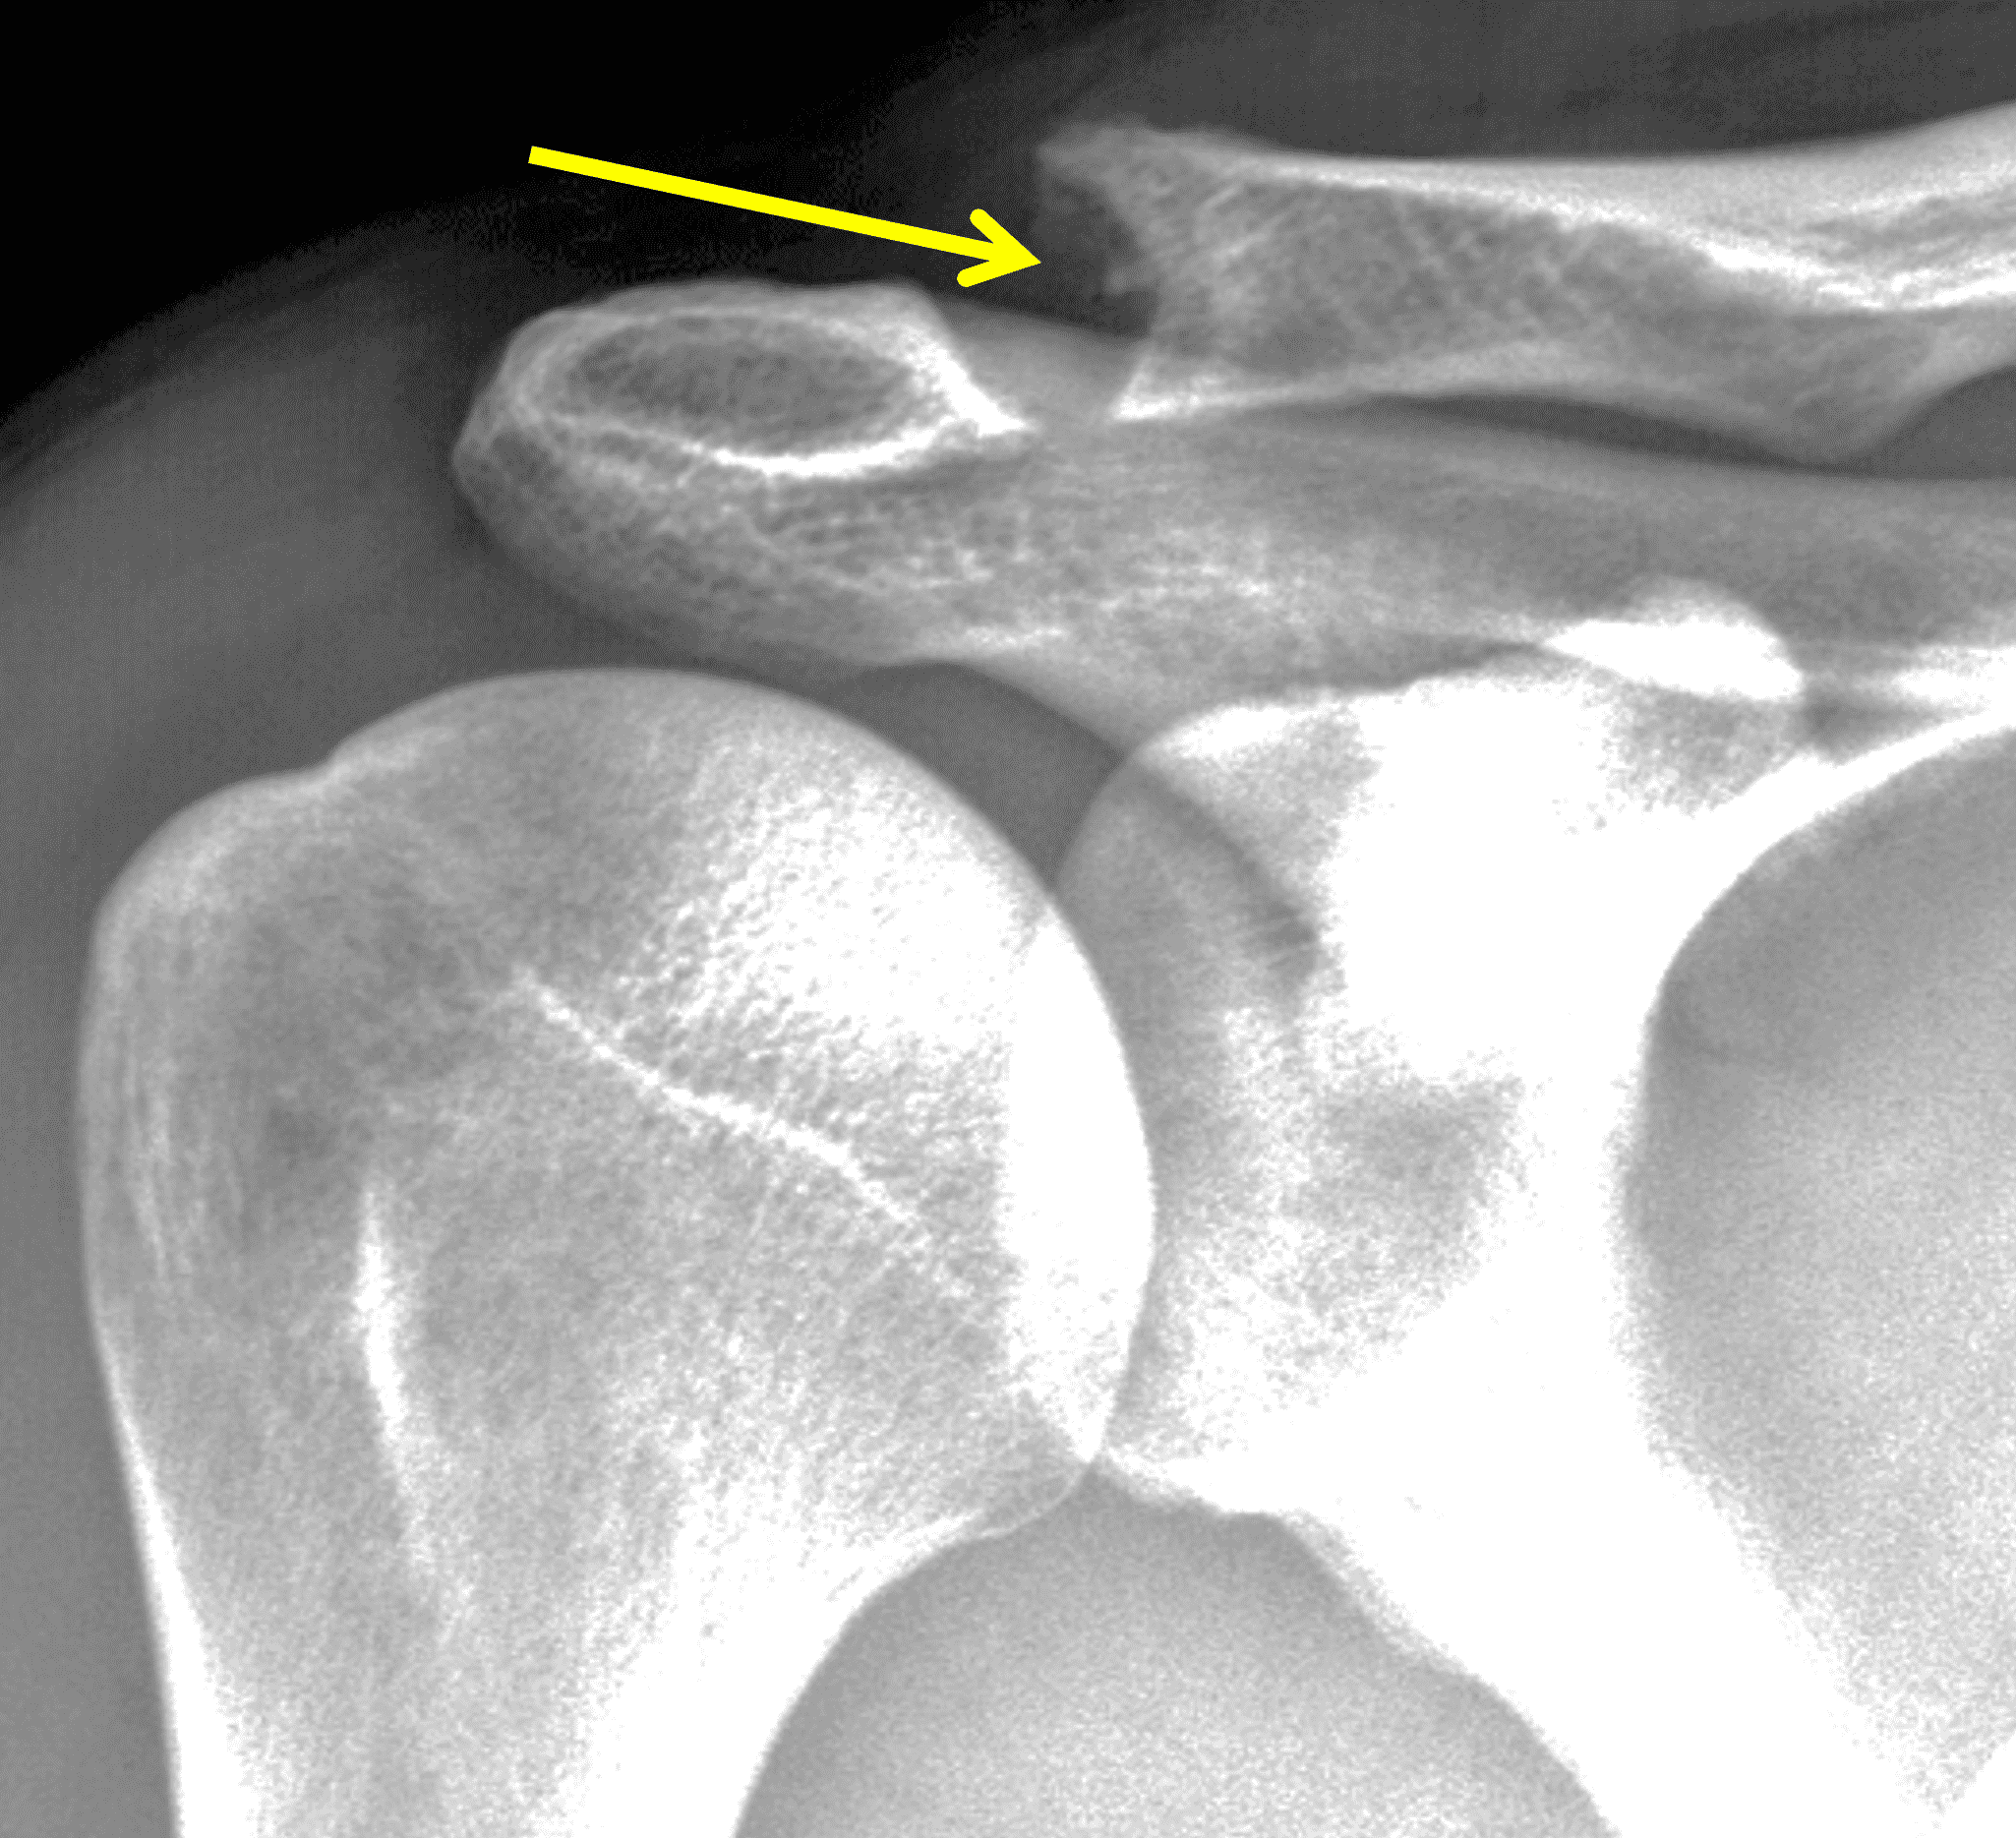

A 49-year-old male, avid weightlifter complains of chronic pain along the superior aspect of his right shoulder. He denies acute trauma. An AP radiograph (Figure 1A), as well as oblique coronal SPAIR (Figure 1B), axial fat-suppressed fluid sensitive (Figure 1C), and oblique sagittal T2-weighted images (Figure 1D) are shown. What are the findings? What is your diagnosis?

Radiographs: Initial radiographs may be normal or show features of other common unrelated AC joint pathology such as osteoarthritis. As inflammation and hyperemia in the distal clavicle progresses, bone density in the distal clavicle can decrease with indistinctness or discontinuity of the subchondral bone plate (Figure 3).  This so-called resorptive phase may also include frank erosions in the distal clavicle or a faint sclerotic line in the medullary space of the distal clavicle parallel to the bone end. Varying degrees of surrounding soft tissue swelling may be visible.  Later, during the late healing phase when symptoms have usually resolved, the distal clavicle may return to a normal radiographic appearance; a sclerotic line parallel to the distal bone end is visible after healing in some cases (Figure 4).  In patients with severe initial bone loss, re-cortication of the resorbed bone and erosions can occur leaving residual bone loss and contour defects in the distal clavicle. While it is typically not a primary modality for the diagnosis of DCO, CT demonstrates the same bone findings as radiographs.

The principle MRI finding of DCO is distal clavicular marrow edema and surrounding inflammation on fluid-sensitive pulse sequences, especially with fat suppression (Figures 3 and 4).2, 9 Marrow changes can occur in patients with normal radiographs,10 in which case a term like “stress/overuse related marrow edema,” might be preferable to “osteolysis.” On MRI, more severe cases may show erosions or cysts in the distal clavicle and loss of the subchondral bone plate in addition to more pronounced marrow and soft tissue edema. A band of low signal paralleling the distal bone end may be present, suggesting a stress fracture line (Figure 5).8 However, a similar appearance can be due to the sclerotic rim surrounding distal clavicle cysts or small erosions (Figure 6). A small effusion or mild synovitis is often present in the AC joint.  Soft tissue edema within and surrounding the AC joint capsule and distal clavicular periosteum may be visible (Figure 3).  Some patients may also show marrow edema (or even erosions) in the anterior acromion, but the changes are typically more severe in the distal clavicle (Figures 5 and 7).2